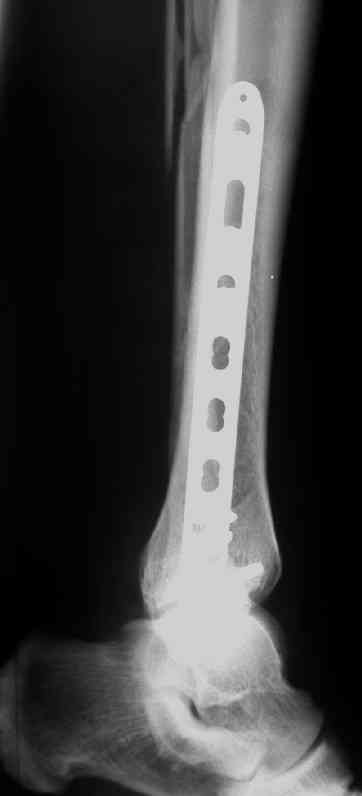

Выполнил MIPO предизогнутой метафизарной LCP

Подход индивидуальный, учитывая массу больного около 130кг, разрешу частичную нагрузку 15-20кг, через 4нед. Rg-контроль, при отсутствии признаков нестабильности полная нагрузка

В этом случае остеосинтез выполнялся малоинвазивно и я не добивался абсолютной стабильности преднамеренно. Стабильность относительная и ст. её зависит от механических свойств импланта;возможно, нужно было взять длиннее пластину, увеличив её рабочую длину